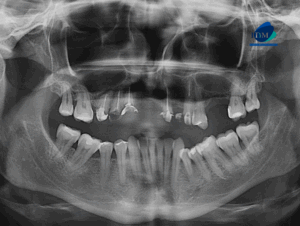

Paciente femenino de 39 años de edad, es referido al Instituto de Diagnóstico Maxilofacial – IDM para evaluación general.En la radiografía panorámica (Figura 1), se